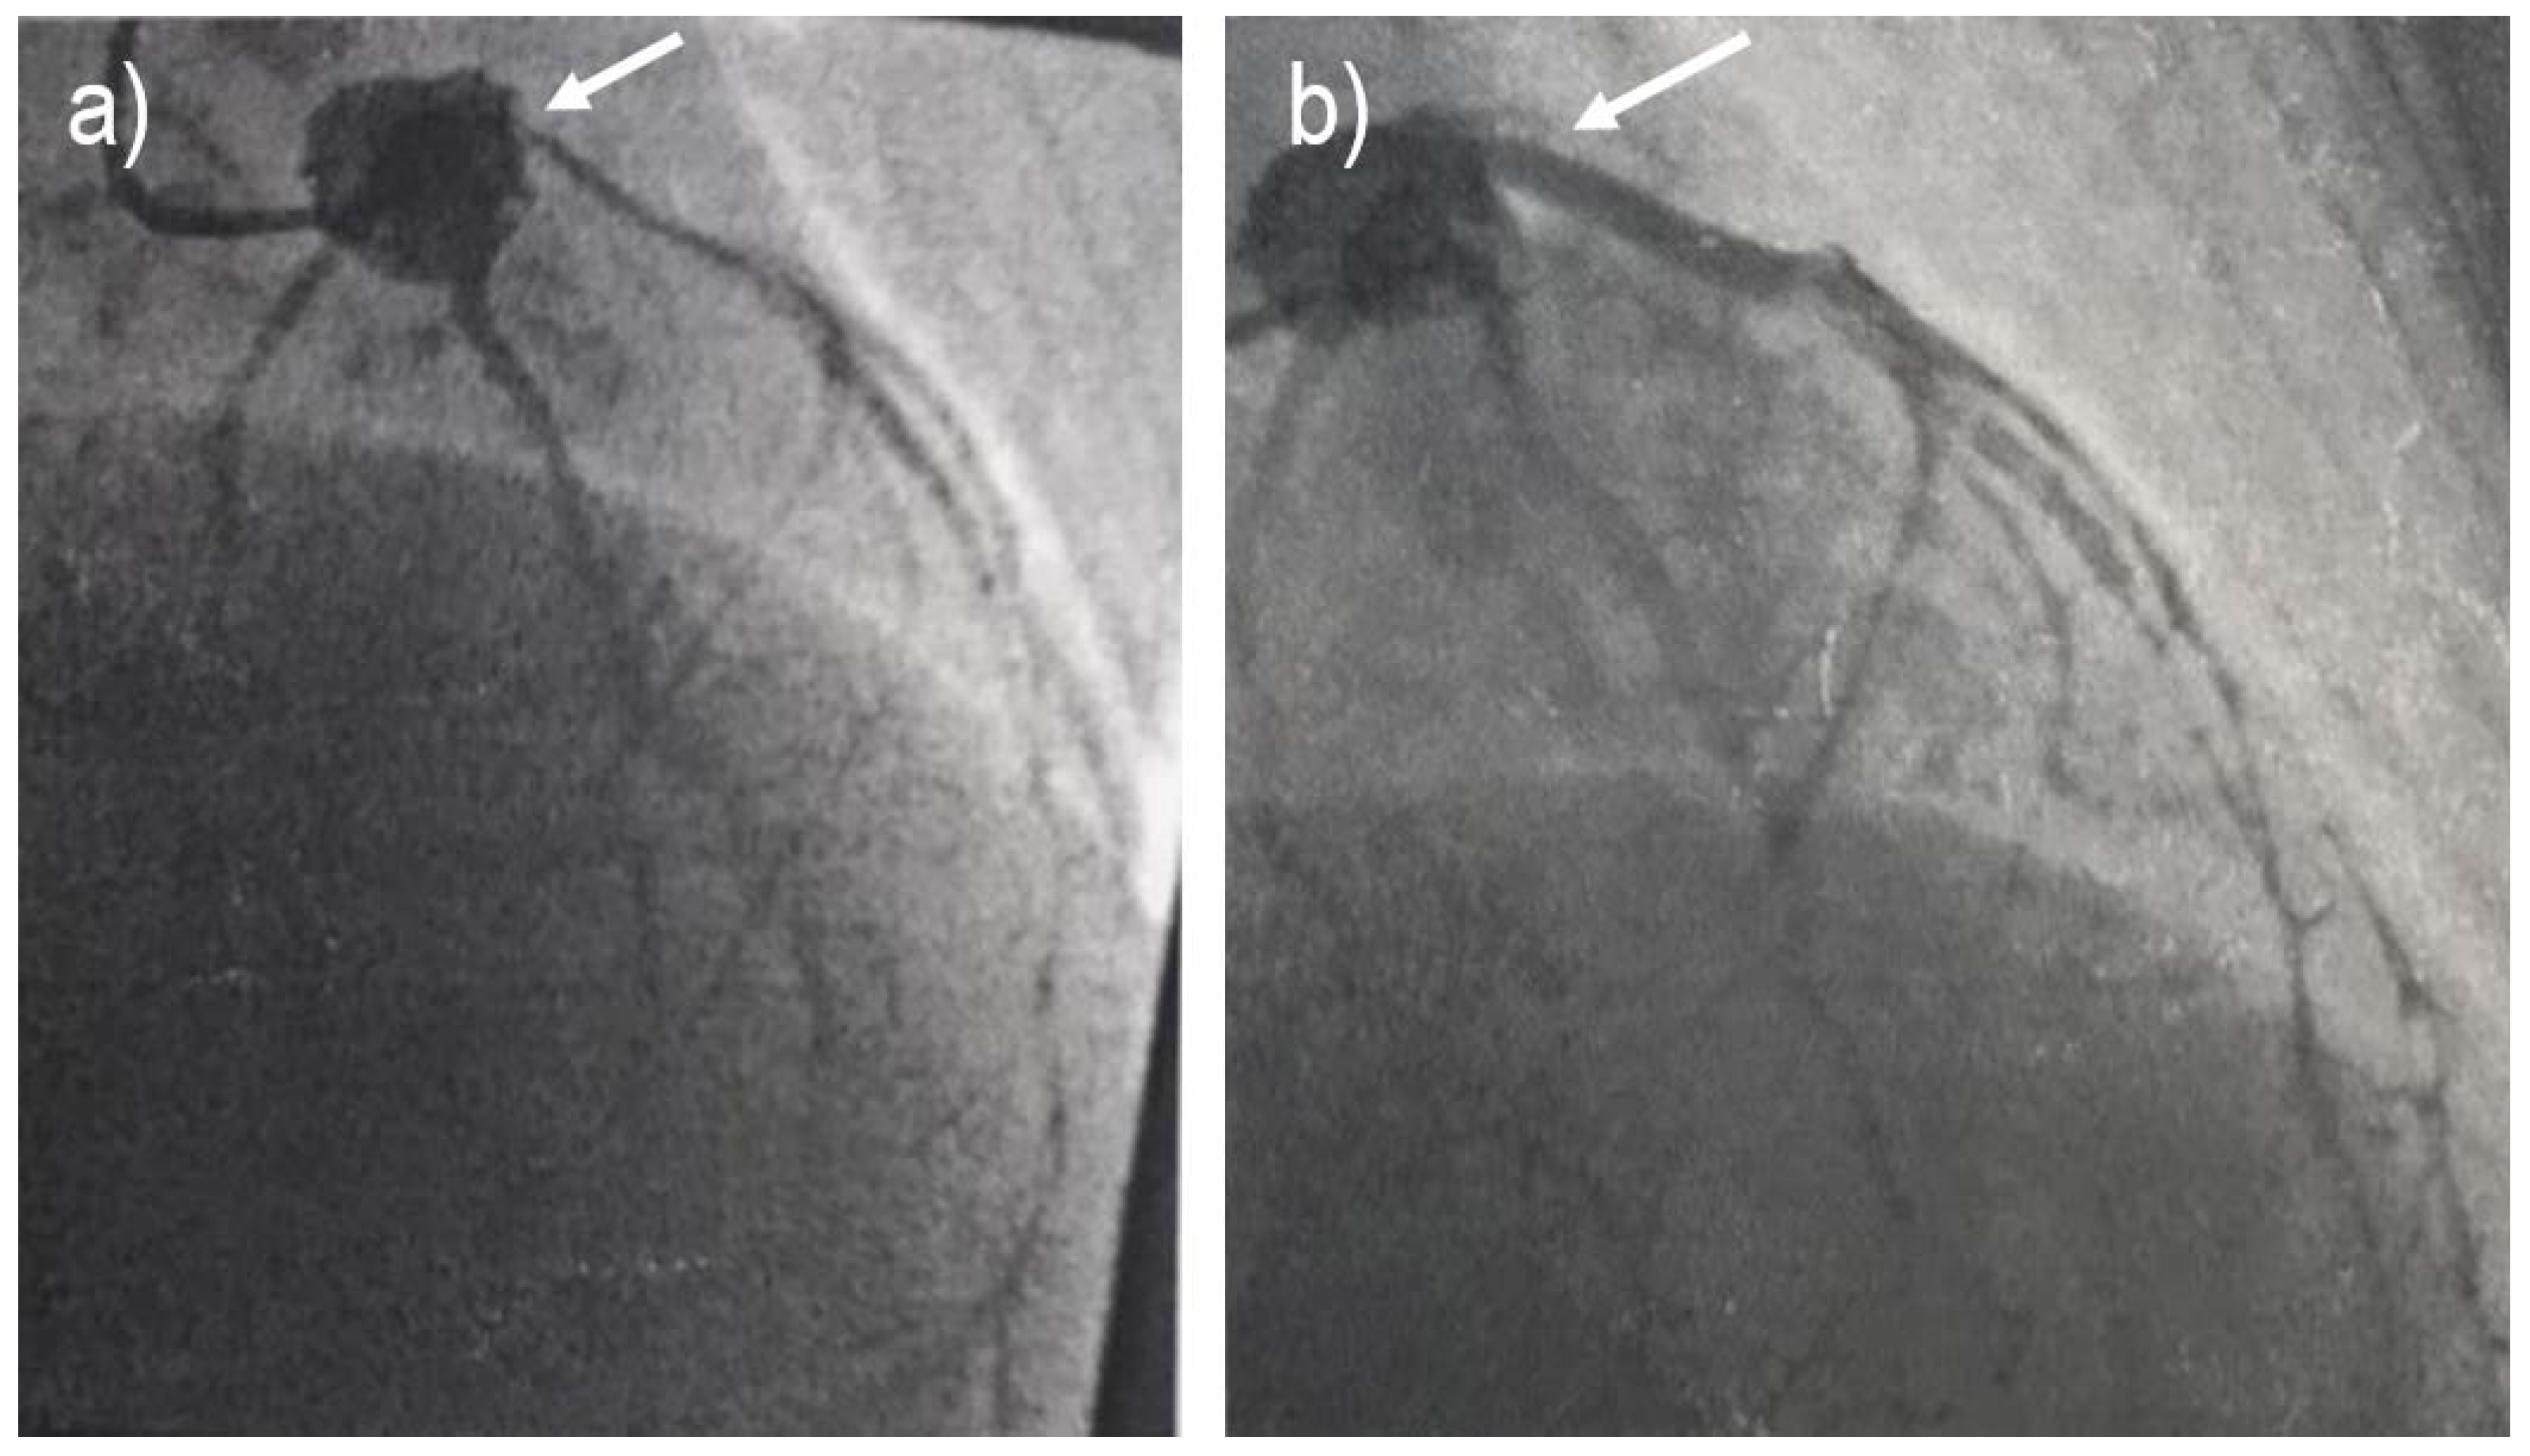

Electrocardiography testing was performed with the results showing ST elevation in leads D1, aVL, and V2-V6 and ST depression in leads D2, D3, and aVF, as displayed in Figure 1.

Figure 1. ECG on admission.